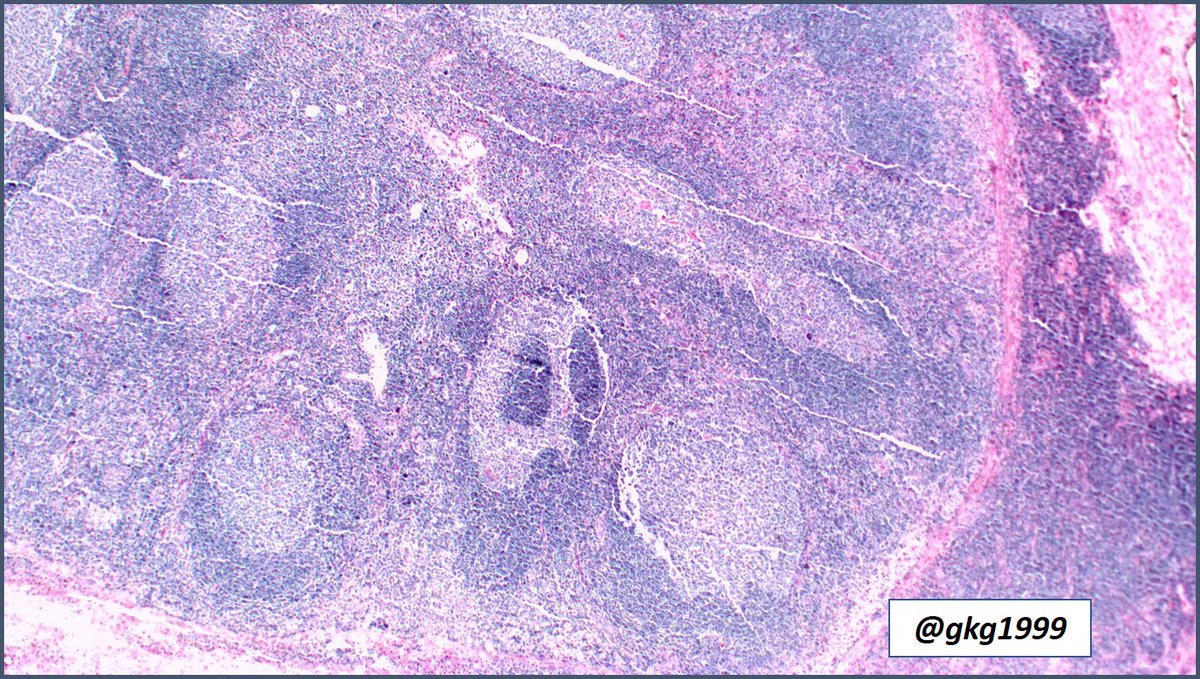

Kimura disease, Warthin-Finkeldey Cells #pathology #pathologists #hemepath #pathboards